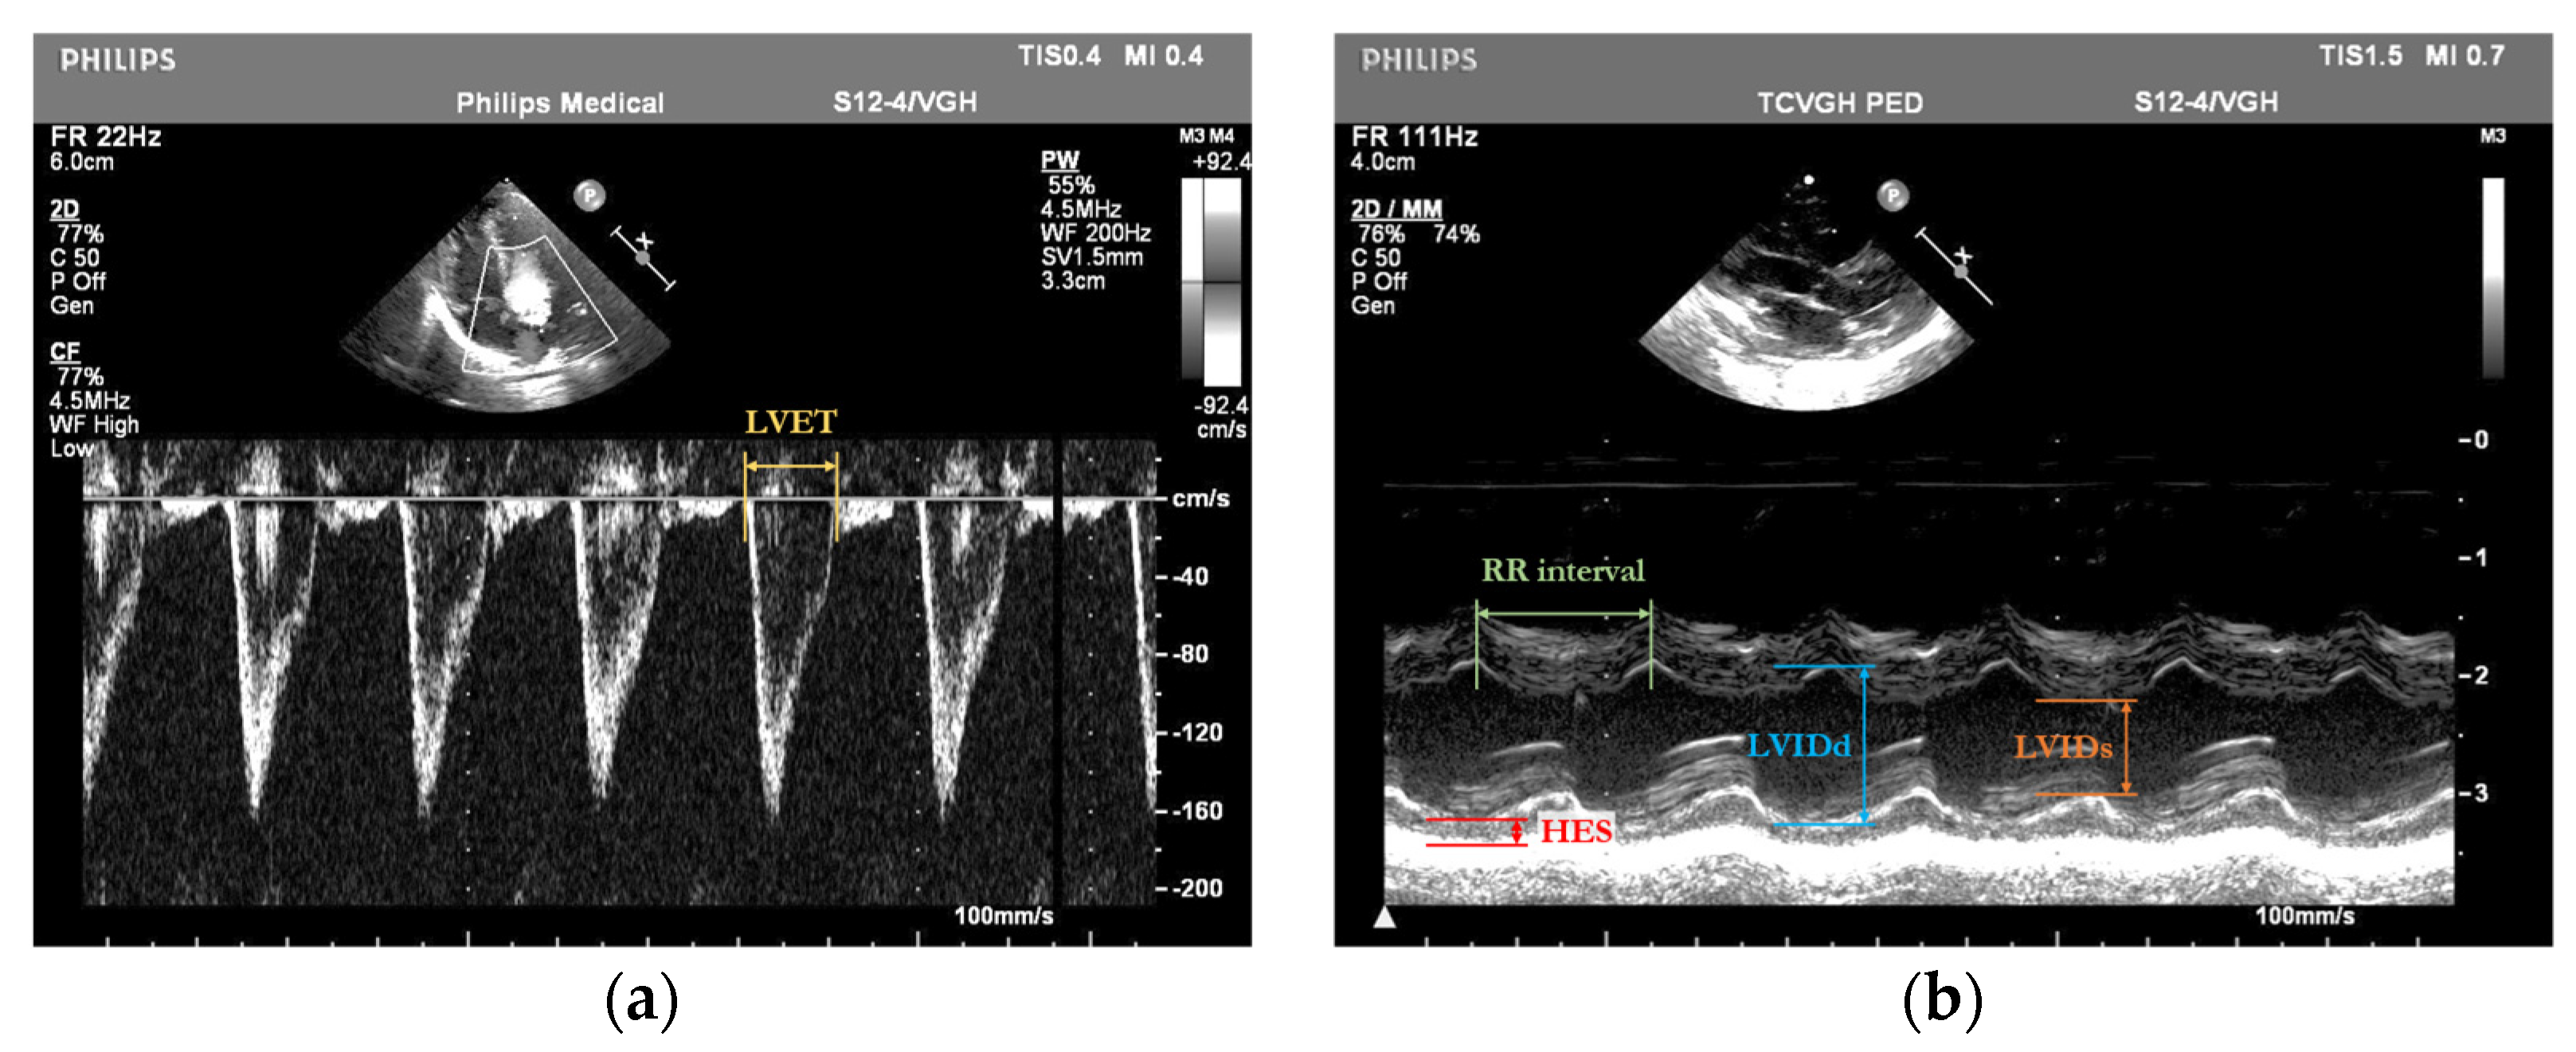

The dataset analyzed in this study was obtained from the Neonatal Intensive Care Unit (NICU) at Taichung Veterans General Hospital (TVGH) in Taiwan. The echocardiographic data were acquired using a high-resolution Philips IE33 cardiovascular ultrasound system equipped with a 4 MHz sector array transducer (Philips S12-4). Standardized probe placement ensured consistent acquisition of M-mode and pulsed-wave Doppler-mode echocardiograms (Figure 2).

The annotation of cardiac parameters, including the LVET, LVIDd, LVIDs, HES, and RR interval, within echocardiograms is shown in Figure 3.

Figure 3. Annotation examples of (a) pulsed-wave Doppler-mode and (b) M-mode echocardiograms showing bounding boxes for LVET, LVIDd, LVIDs, HES, and RR interval.